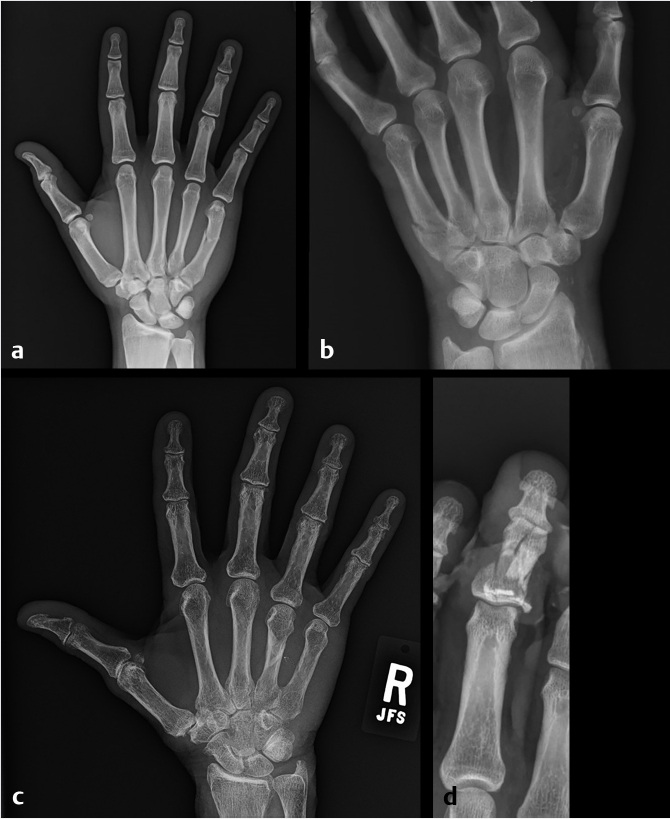

In the radiographic evaluation of hand fractures, plain radiographs are the mainstay of diagnosis. All hand injuries should be evaluated with anteroposterior (AP), lateral, and oblique radiographs. These three views are essential for visualizing the small bones in the hand to best characterize, and avoid missing, any fractures. In addition, it is best to order radiographs as specific to the injury as possible for the best view. For example, if the small finger has a deformity and a fracture is suspected, a three-view series of the small finger will yield higher quality images than a three-view series of the hand. This is because the sharpest images are obtained when the X-ray beam is centered over the area of interest; for example, hand series X-rays center the beam over the middle finger metacarpal which contrasts with dedicated finger series which center over the proximal phalanx. As a result, the AP image of a hand will capture the small finger slightly supinated potentially obscuring subtle fractures (Fig. 24‑2). In some injury patterns, additional radiograph views are useful, such as hook of the hamate view, navicular view, Robert’s view for a true AP view of the thumb, and dynamic studies such as the clenched fist view (Fig. 24‑3). 1 , 2 Computed tomography (CT) imaging is required only occasionally for fracture evaluation. Indications for CT imaging are primarily for operative planning in highly comminuted, intra-articular fractures. Magnetic resonance imaging is likewise rarely required for hand fractures, indicated mainly for detecting occult scaphoid fractures or early avascular necrosis such as in Kienbock’s disease. 2 While ultrasound imaging can be useful for soft-tissue hand injuries, it does not have utility in evaluating fractures.

When reading the radiographs, the treating physician should be able to accurately diagnose and describe the type of fracture sustained. This not only allows for determination of appropriate treatment but also ensures accurate and efficient communication with other physicians. Possible fracture patterns include transverse, oblique, spiral, and comminuted (Fig. 24‑4). Fractures are described by identifying the type of fracture, whether it is open or closed, commenting on the degree of comminution if present, the presence and direction of fracture fragment angulation, whether the fracture is apex-volar or apex-dorsal, whether there is any shortening or segmental loss of the overall bone length, measurement of any step-off of the fracture fragments, description of any rotational deformity, quantifying any articular surface involvement, and whether there is any associated joint dislocation (Fig. 24‑5).